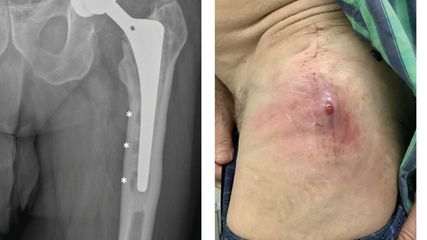

Einzeitiger und mehrzeitiger septischer Endoprothesenwechsel

Die periprothetische Infektion (PPI) stellt eine der gefürchtetsten Komplikationen im Bereich der Orthopädie und Traumatologie dar. Sie ist verbunden mit hohen Morbiditäts- und ...